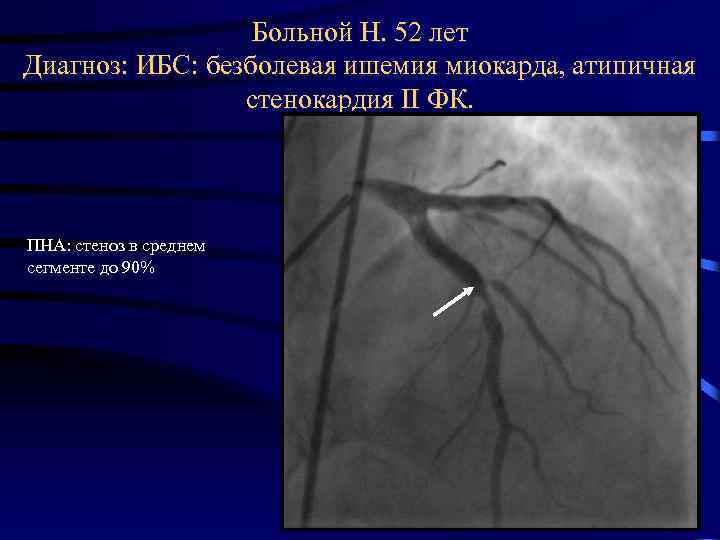

Больной Н. 52 лет Диагноз: ИБС: безболевая ишемия миокарда, атипичная стенокардия II ФК. ПНА: стеноз в среднем сегменте до 90%